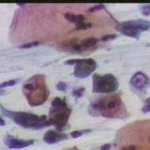

Κυτταρολογικές εικόνες προσβολής του τραχήλου της μήτρας από ιούς κονδυλωμάτων:

Κυτταρολογικές εικόνες προσβολής του τραχήλου της μήτρας από ιούς κονδυλωμάτων: Ασθενής 23 ετών, υποτροπές κολπίτιδος εναλλασσόμενης αιτιολογίας (κολπίτις μικροβιακής αιτιολογίας, κολπίτις από Candida albicans). Τώρα: pH 5, Στο νωπό παρασκεύασμα αρραιή μικροβιακή χλωρίδα. Κολποσκοπικώς επίπεδο μωσαϊκό στο πρόσθιο χείλος. Κοιλοκυττάρωση σε επιφανειακά και διάμεσα κύτταρα. Στην μικροβιοψία τραχηλίτις, υπόνοια για HPV.